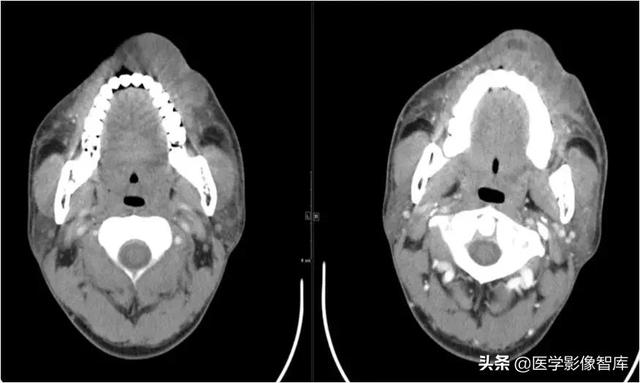

咀嚼肌间隙、翼下颌间隙、颊间隙

男,31岁,患者约3天前出现右侧面部口角区局限性肿胀,无明显触压痛,既往右侧下颌后牙区阵发性锐痛,曾自行口服消炎药处理,自诉牙痛症状无明显缓解,约3天前牙痛症状加重,伴夜间痛,后自觉右侧面部肿胀,约2天前开始发热,体温39.8℃。